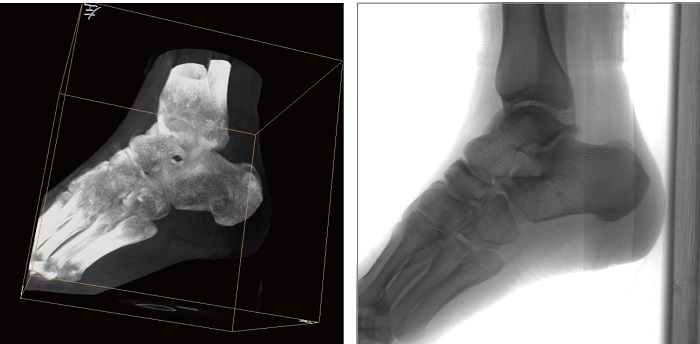

1、術(shù)中三維成像。PLX C7500A三維C型臂的術(shù)中三維成像和類CT切片圖像提供更全面的手術(shù)診斷信息,輔助醫(yī)生進(jìn)行術(shù)中準(zhǔn)確評估判斷諸如骨折復(fù)位情況和內(nèi)植入螺釘?shù)某叽绾臀恢茫WC了手術(shù)高精度地完成。

3、穩(wěn)定全面的圖形采集。PLX C7500A三維平板C形臂具有等中心掃描技術(shù),始終保持拍攝主體處于射線束的中心,避免C臂機(jī)架的橫縱方向的運(yùn)動,從根源上減少了運(yùn)動偽影了產(chǎn)生,提升圖像的清晰度。同時(shí)可190°三維采集角度,電驅(qū)動沿軌道滑轉(zhuǎn),提供高精度、全方位的三維圖像及類CT切片圖像信息。